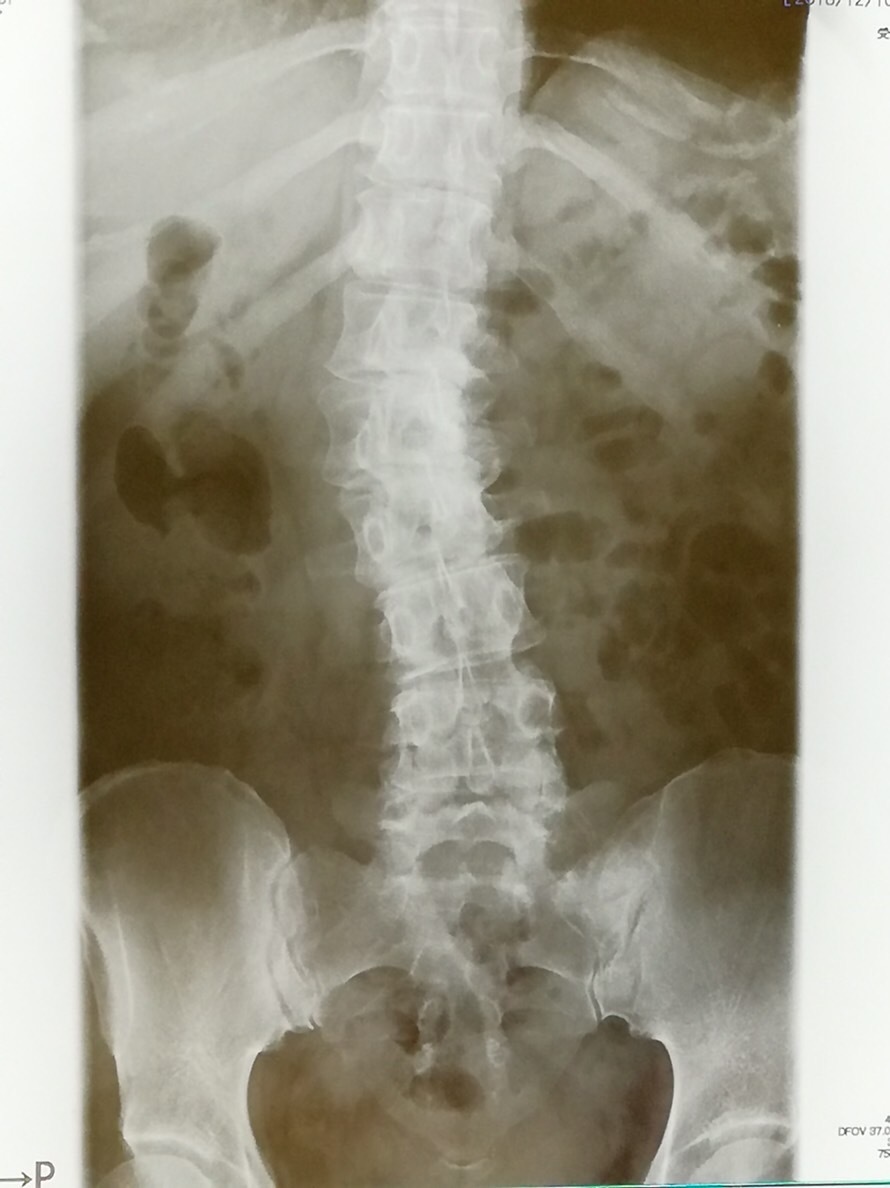

正常な背骨は前後からみると真っ直ぐに連なっていますが、側弯症では、背骨が左右に曲がって、捻れています。

コブ角25°以下では経過観察と側弯体操を行います。

コブ角25°以上だとミルウォーキーブレースやボストンブレースという装具による矯正を行います。

コブ角45~50°を超えるものは手術が適用されることがあります。